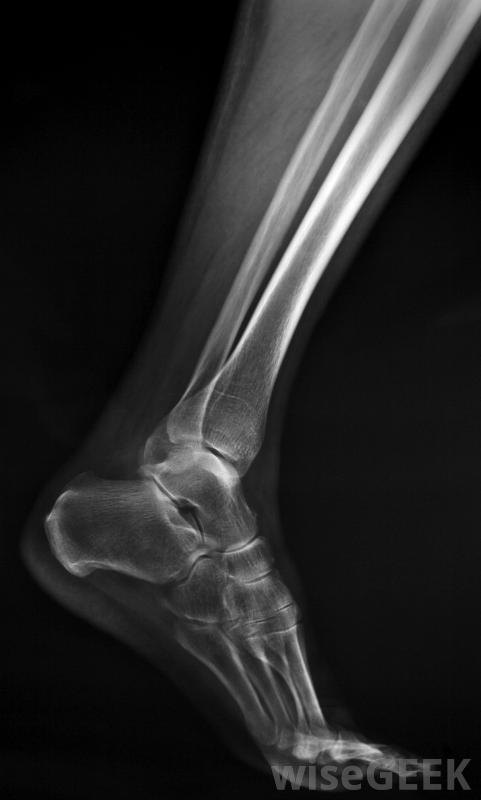

腓骨手术治疗腓骨骨折或缺损,小腿骨,或获取移植材料。手术的具体细节取决于患者为什么需要手术。可能由足踝专家、骨科医生进行,或者是神经外科医生。康复时间从几个小时到几周或几个月不等,通过物理疗法来重建患肢的力量。如果患者想了解更多关于治疗方案和医生建议的信息,他们可以在手术前向其他外科医生寻求第二意见腓骨是小腿中较薄的长骨,需要进行腓骨手术的一个常见原因是修复骨折沿着小腿外侧延伸至脚踝,通常在踝关节附近骨折。有些骨折可以通过石膏固定修复,但其他骨折可能需要手术治疗。这包括在骨骼编织时用钉住骨头使其稳定,以及检查韧带、肌腱的损伤,这种损伤可以在腓骨手术中得到纠正。

修复骨折是进行腓骨手术的最常见原因腓骨植入身体其他部位。在骨移植手术中,病人被麻醉,同时采集材料样本并植入新的位置,如颌骨。这可以在严重损伤后重建骨骼,或者作为矫正手术的一部分来解决先天性畸形。在这种情况下,手术团队可能会包括重建外科医生来创造一个平滑而均匀的外观。手术所需的麻醉水平可能会有所不同。对一些人来说,只有清醒镇静和局部麻醉剂是必需的。其他人需要全身麻醉以确保病人的安全,这通常会导致较长时间的恢复。患者应在腓骨手术后尽快进行活动,以降低血栓的风险,并开始重建腿部的力量。建议他们考虑将物理治疗作为恢复的一部分